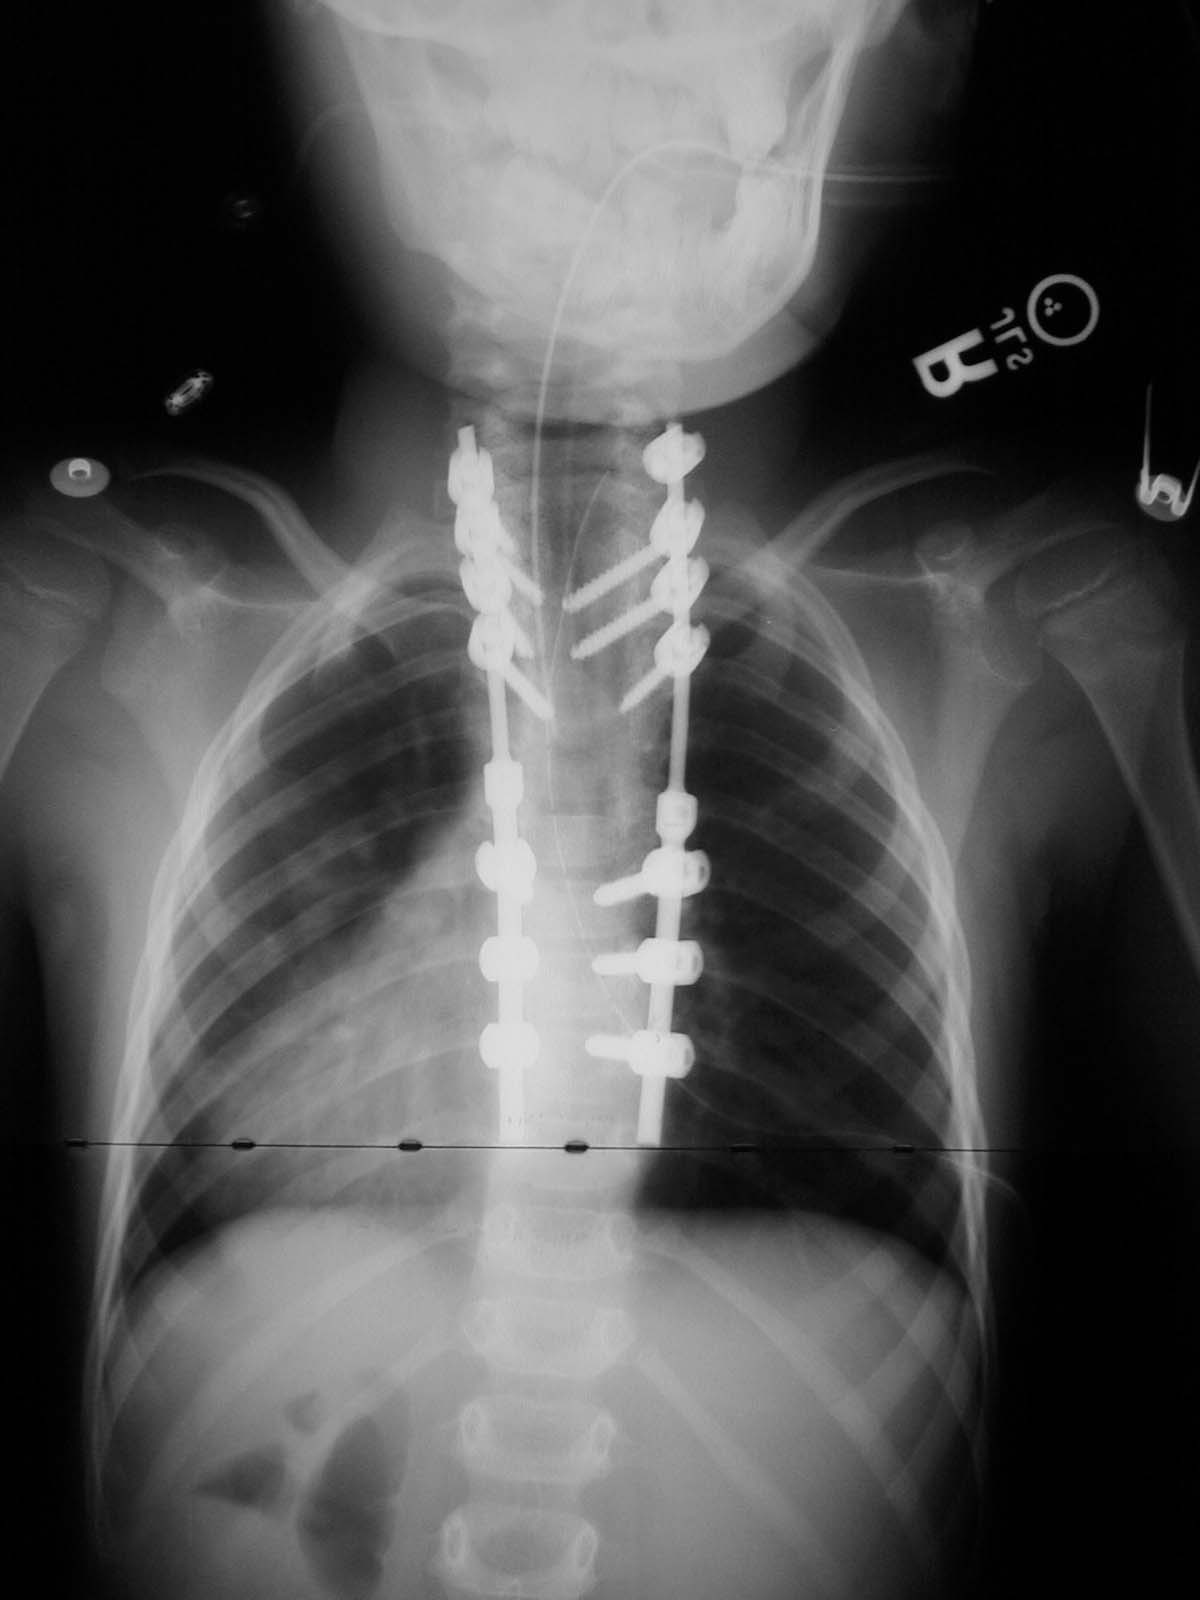

Back-side view taken during surgery on 1/27/05.  Here you get a good view of the pedicle screws and rods.

The pictures below are x-ray's of Nick's spine so you can see the progress achieved.  You can click on a picture to see a larger version of it.